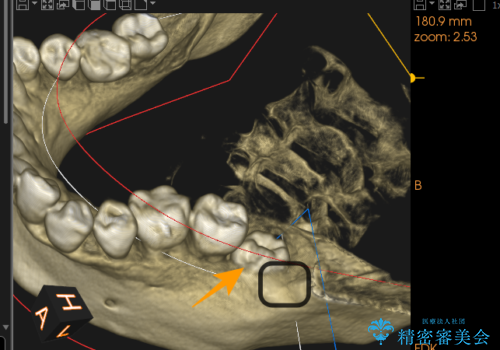

2. 【埋伏智歯と埋伏智歯の過剰歯の抜歯】埋まっている親知らず2本の抜歯の治療中

2.